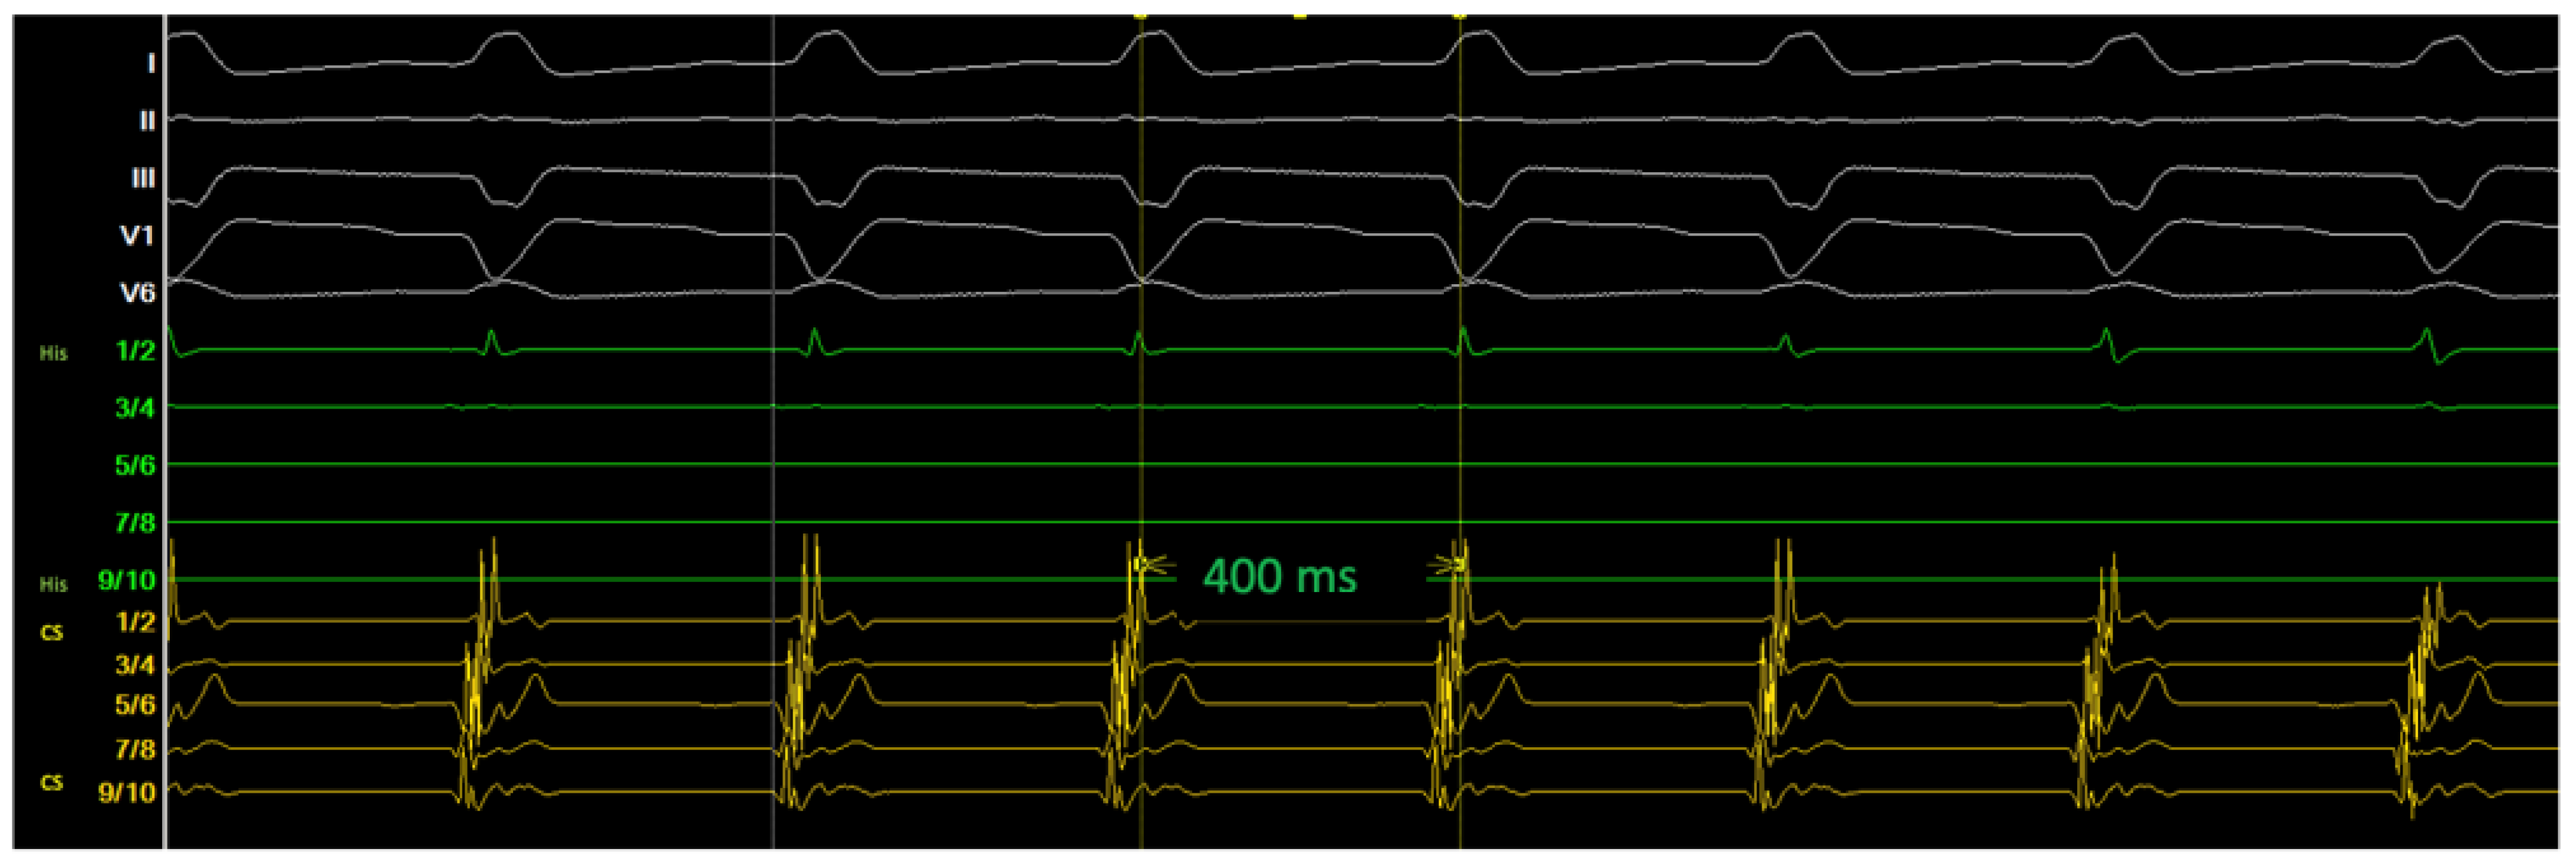

2. Method and Results

2.2. Diagnostic Workup